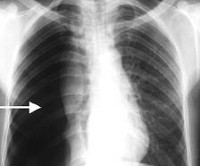

Первостепенное значение в диагностике отводится лучевым методам: рентгенографии и рентгеноскопии грудной клетки, которые позволяют оценить количество воздуха в плевральной полости и степень спадения легкого в зависимости от распространенности спонтанного пневмоторакса. Контрольные рентгеновские исследования проводятся после любых лечебных манипуляций (пункции или дренирования плевральной полости) и позволяют оценить их эффективность. В дальнейшем с помощью КТ высокого разрешения или МРТ легких устанавливается причина спонтанного пневмоторакса.